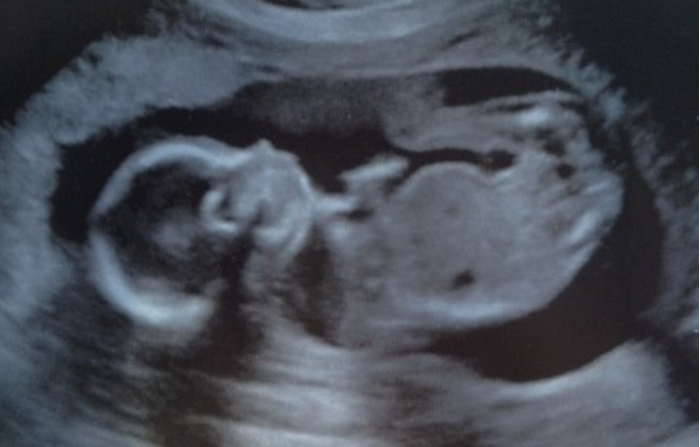

Women in Georgia can currently seek an abortion during the first 20 weeks of a pregnancy. A fetal heartbeat is generally detectable at around six weeks, before many women know they are pregnant.